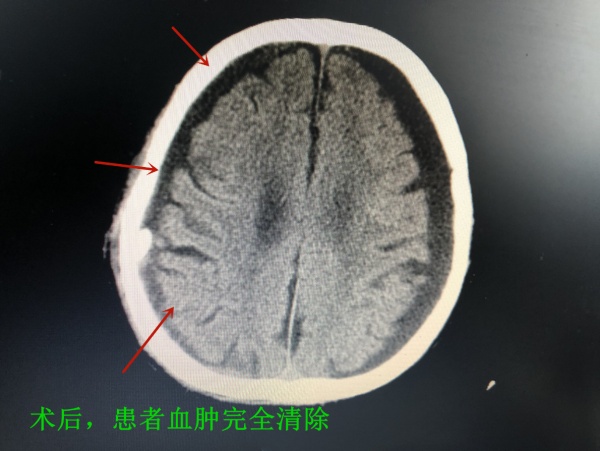

为免病情加重引发脑疝危及生命,岑波建议立即为老人进行手术清除血肿。在家属的高度信任和认可下,岑波带领手术医师陈俊瑜、郝鸣,为老人顺利实施了右侧硬膜下血肿钻孔引流微创手术。

术后经一周精心医护,老人精神矍铄,左侧肢体肌力恢复正常。